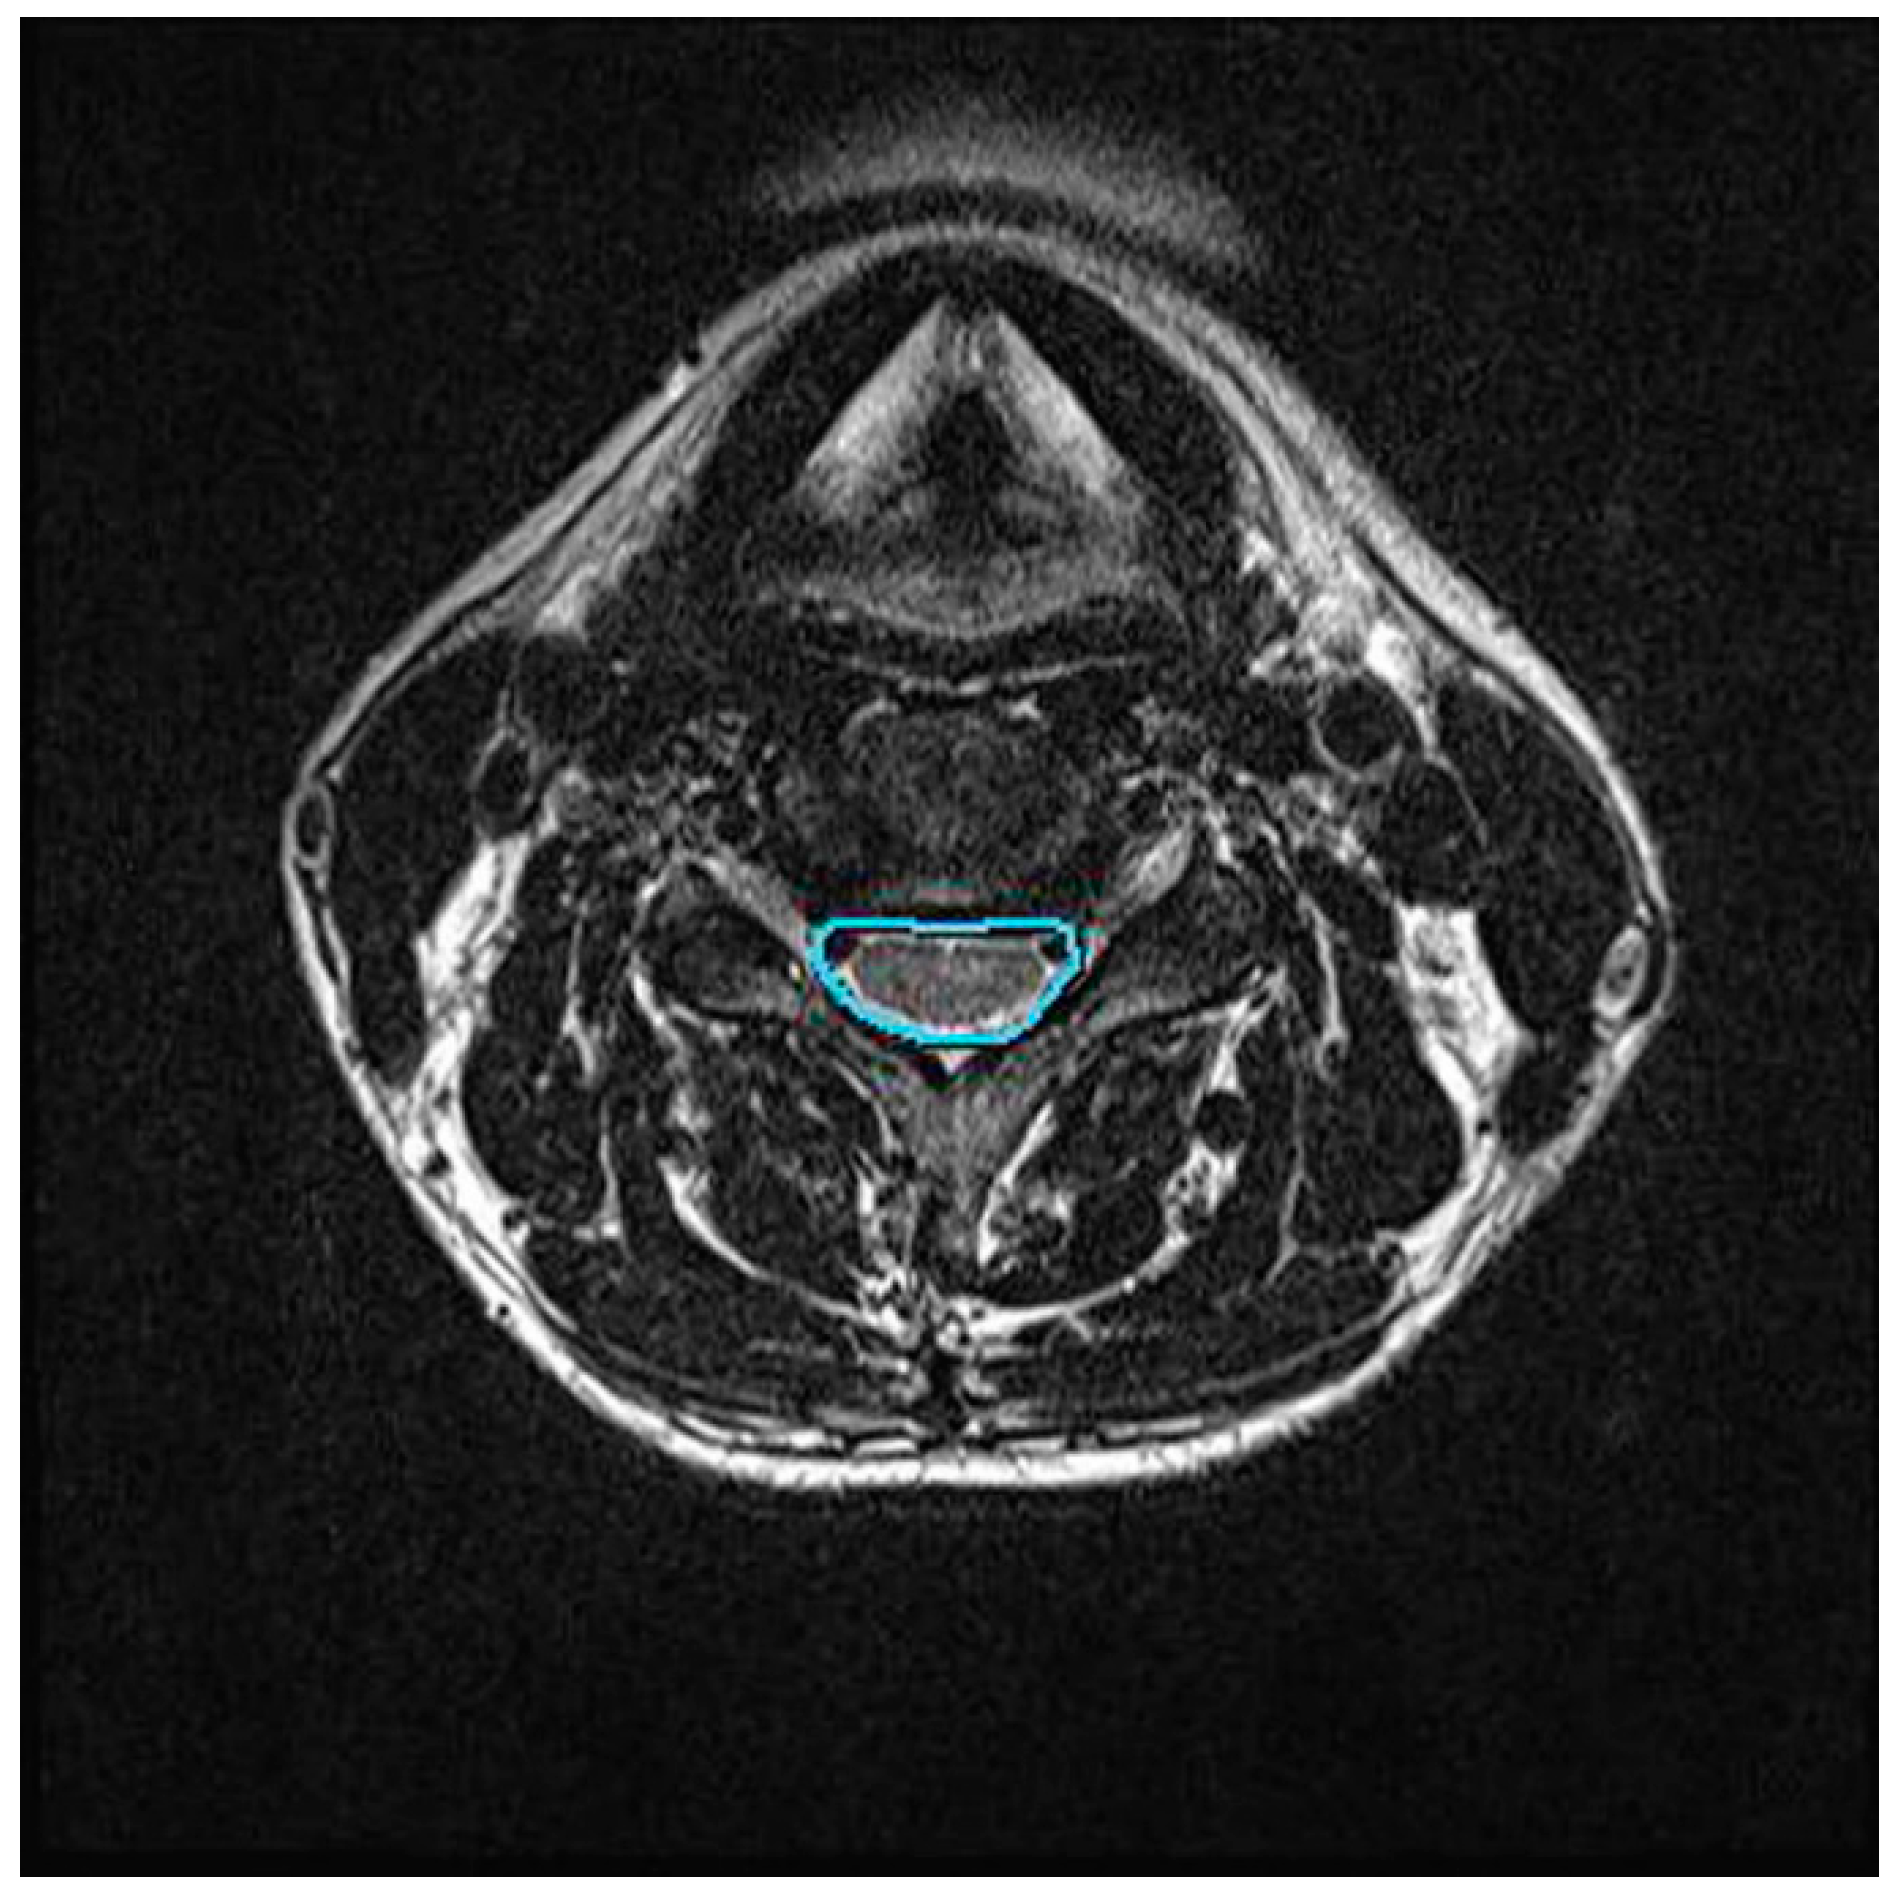

2.4.2. Central Canal Area Assessment

We assessed the changes in the area of the cervical central canal before and after cervical traction. Using the MR T2-weighted images, the axial image with the greatest disc level associated with the greatest neurologic compression was selected for measurement. In this study, the C5/6 intervertebral disc level was selected. Digital measurement of the central canal area outline was performed by tracing the boundaries of the dural cross-sectional area in the axial MRI at the C5/6 disc level (Figure 3). Measurements were conducted by a single-blinded radiologist with more than 10 years of experience. Each measurement was repeated three times by the same radiologist to enhance repeatability.

Figure 3.

Central canal area in axial view of cervical spine MRI.

The change of the central canal area in cervical spine MRI was significantly greater in the C-LCCT group (p < 0.01). However, there was no significant change in the central canal area in the TT group after treatment (p > 0.05).